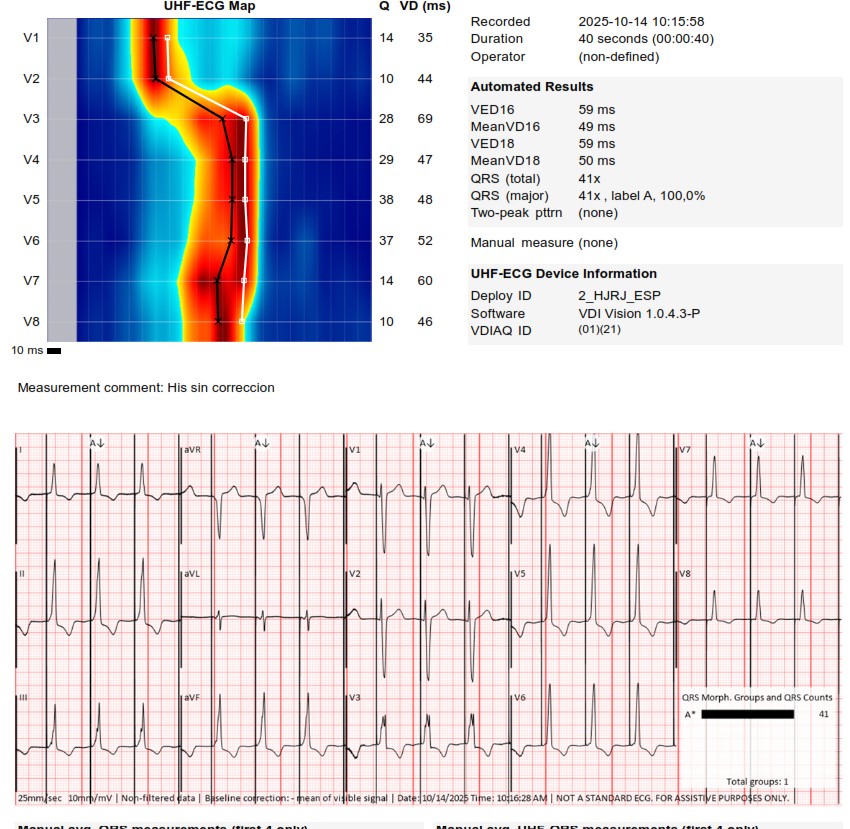

I strongly support HBP, but in this case,the great improvement in QRS didn't correct the asynchrony measured with UHF ECG.We opted for LBBAP despite the RV delay.The final programming AV 70 ms and fusion with native rhythm achieved the best result with UHF ECG(very useful tool)

Challenging LOT CRT case. Final UHF ECG recordings very satisfactory @curilakarol @MirekNavratil1 #Epeeps

An interesting case was shared today. UHF-ECG can help to enhance the decision-making in less textbook-type cases.

These are UHF maps of the two patterns. The second one is a little bit deeper into the septum,